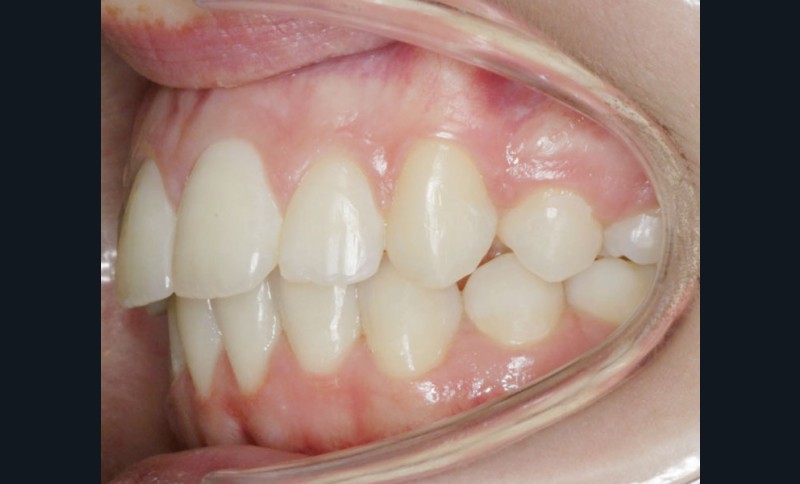

Son profil convexe s’inscrit dans un contexte de rétrognathie hyperdivergente associée à une proalvéolie et un encombrement maxillo-mandibulaire.

• Obtenir des rapports squelettiques de classe I par réponse de croissance mandibulaire.

• Résoudre l’encombrement intra-arcade par extractions dentaires.

• Obtenir un guide antérieur fonctionnel par idéalisation des rapports incisifs.